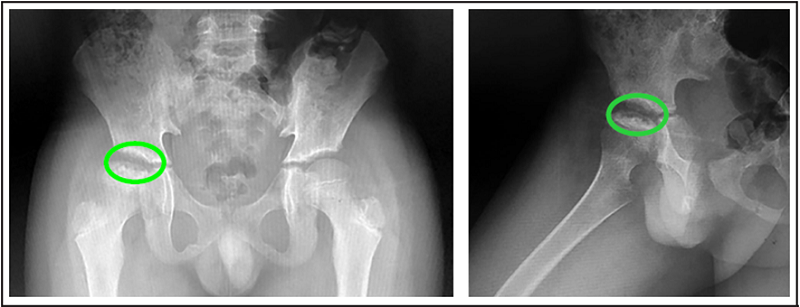

Actualmente el paciente no tiene dolor. En la última radiografía, tras año y medio de su diagnóstico (figura 3), no ha presentado más crisis vaso oclusivas y se encuentra sin limitación funcional.